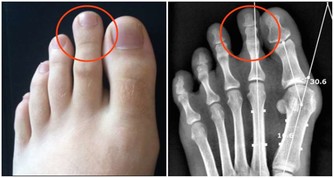

近些年來,突發猝死的事故越來越多,經常能在網上爆出突然猝死的新聞。這都是因為現代人生活節奏快、工作強度大,經常加班熬夜,生活作息又不規律,給心臟造成了極大的負荷,久而久之出現心血管疾病的人正在逐年上升。

其實,心臟出問題之前,一般會給我們發出很多“求救信號”,今天我就來教大家辨別一下這些“求救信號”,早發現早控制。